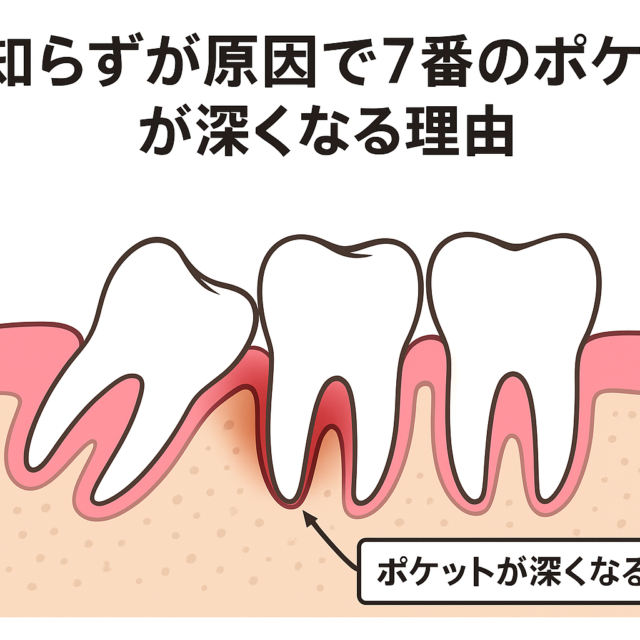

歯の健康向上: 歯並びや咬み合わせの問題が解消されることで、歯の清掃が容易になり、むし歯や歯周病のリスクが減少します。正しい咬み合わせは歯の健康維持に寄与します。

長期的な健康の維持: 正しい歯並びと咬み合わせは、長期的な口腔健康の維持に寄与します。矯正治療を受けることで、将来的な歯のトラブルや関連する健康問題のリスクが低減します。